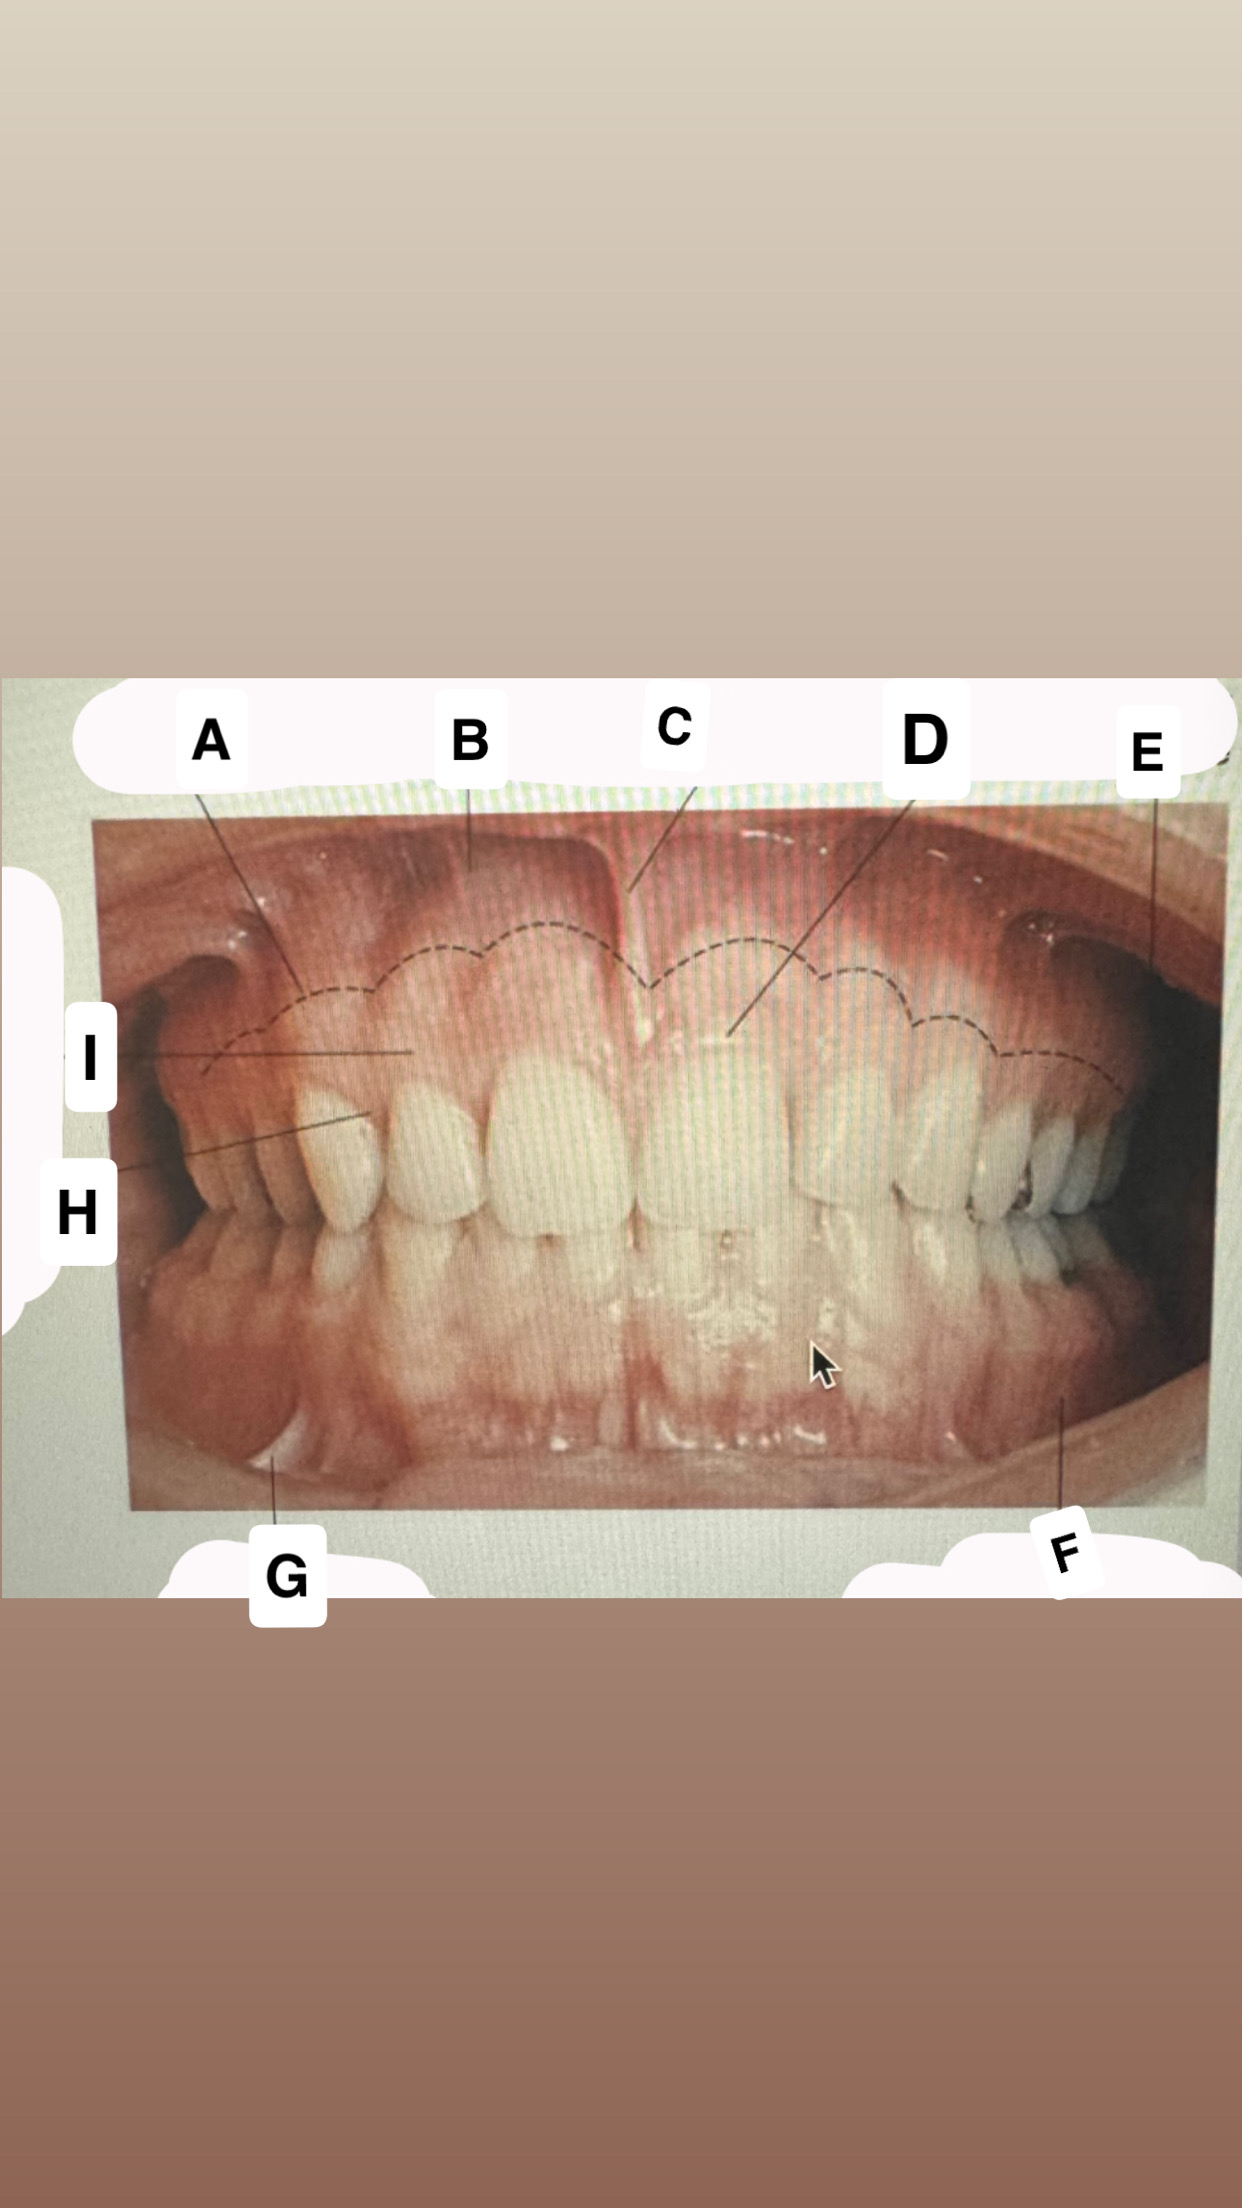

<p>Identify A</p>

buccal frenum

Mucogingival

junction

<p>Identify B</p>

Alveolar

mucose

<p>Identify C</p>

Maxillary labial frenum

<p>Identify D</p>

Marginal gingiva

<p>Identify E</p>

Maxillary vestibule

<p>Identify F</p>

Mandibular vestibule

<p>Identify G</p>

Mandibular buccal frenum

<p>Identify H</p>

Interdental-gingiva

<p>Identify I</p>

Attached gingiva